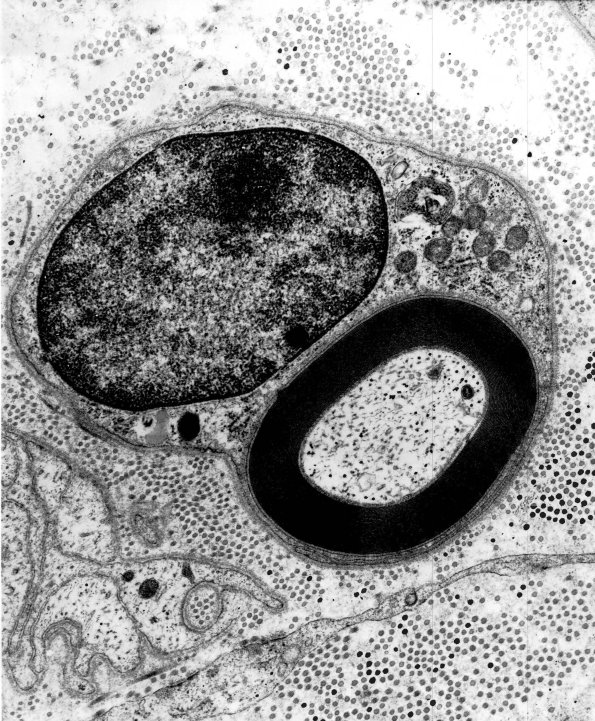

1A1,2 This small axon has a normal appearing myelin sheath in which myelin periodicity is uniform and tightly compacted. (electron micrographs)